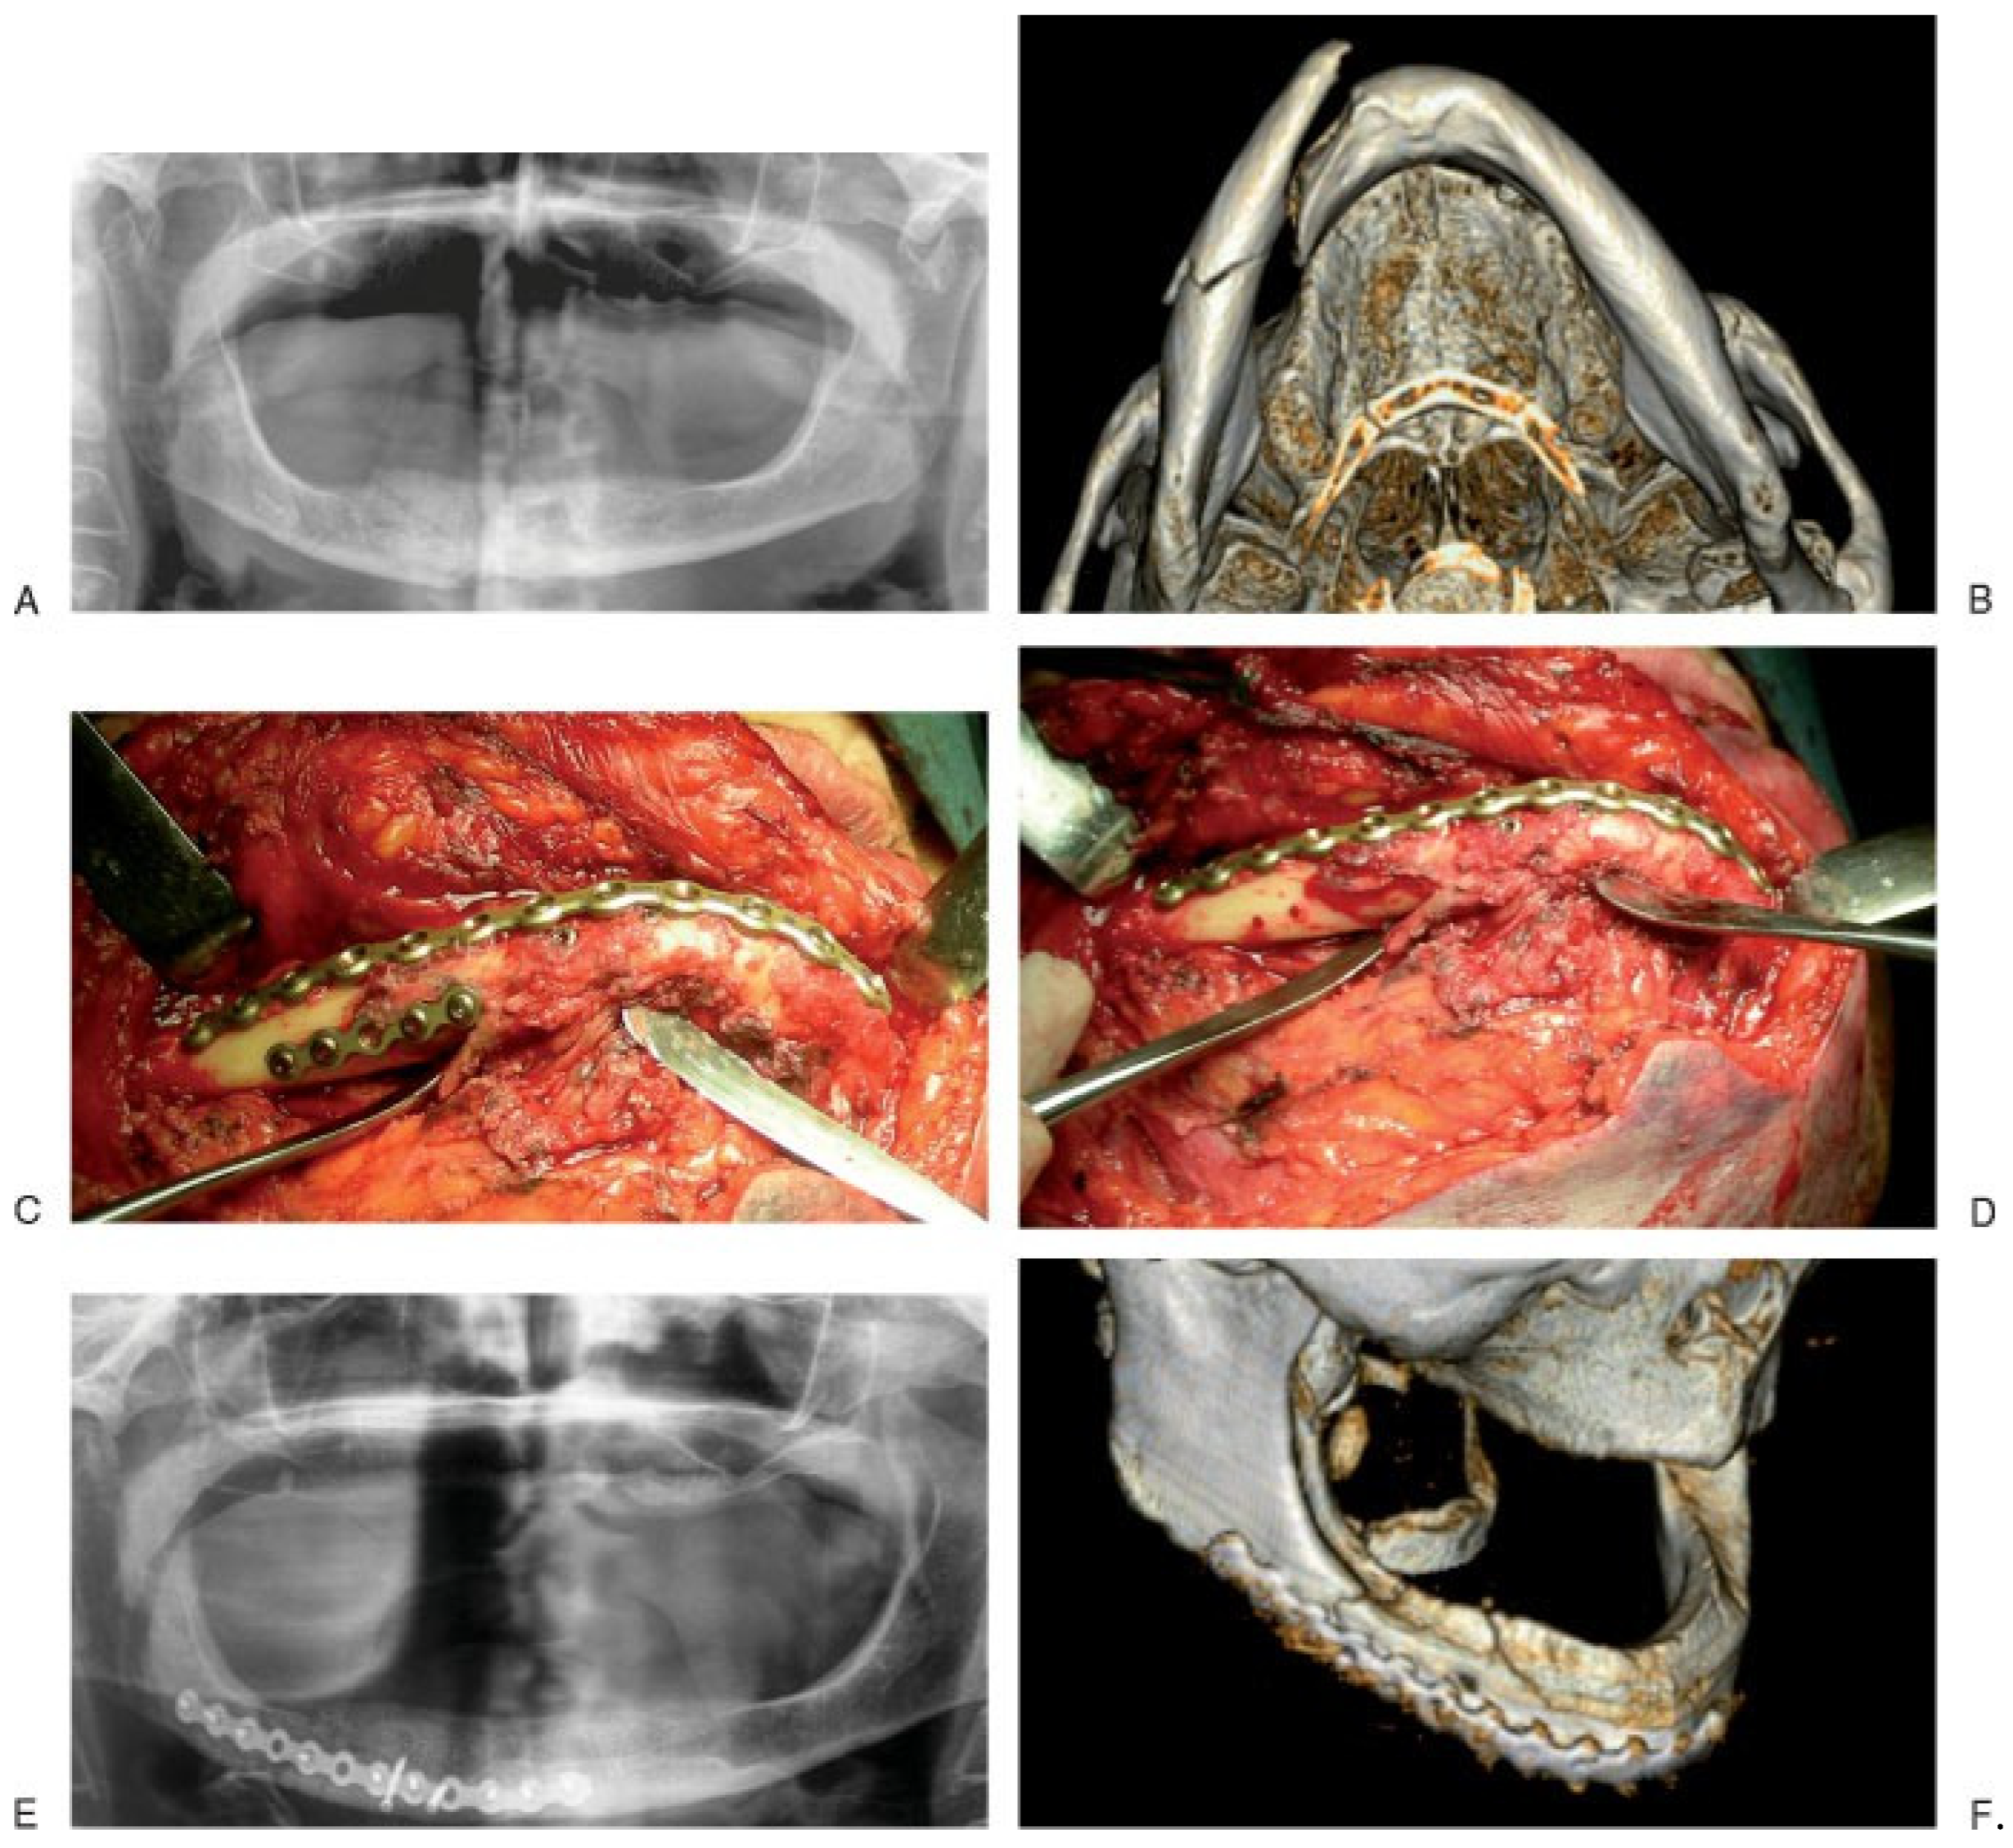

The second group included eight patients treated using 2.4-/-2.5 mm locking bone plates (Table 3; Figure 4). One patient was male, the other seven were female; age ranged from 51 to 89 years, with a mean of 77 years. Causes of fracture included five accidental falls, two motor vehicle accidents, and one trauma secondary to assault. Reported cases showed six fractures located at the body region, one at the symphysis, and one at the angle of the mandible. Of the eight fractures studied, three were bilateral at both the body regions, two were unilateral comminuted located at the mandibular body and angle, and the other three were unilateral simple fractures. All fractures were displaced except one. Fracture displacement was mild in three cases; of these, two were unilateral. In the two comminuted fractures, the amount of displacement was severe with an important override of the bone fragments. The three remaining cases were unilateral or bilateral fractures located at the mandibular body regions with moderate or severe displacement of the fractured segments. All surgical approaches were extraoral: seven submandibular (of these, three were bilateral) and one submental. Temporary fixation was applied to seven fractures before the final fixation plate was adapted and secured. In all cases, temporary fixation devices were removed after application of the final fixation (Figure 5A–E).

Figure 5. A case of bilateral fracture of the atrophic mandibular body. (A) Pretreatment panoramic radiograph showing mandibular body fractures. (B) Intraoperative photograph showing the 2.5-mm lock bone plate placed and adapted on the fracture site (bridging); meanwhile fracture segments were reduced using temporary fixation devices. (C) Intraoperative photograph showing the 2.5-mm lock bone plate fixed and stabilized on the fractures. (D) Postoperative panoramic radiograph demonstrating the final fixation of the fractures provided by the plate. (E) CT scan with 3-D reconstruction.